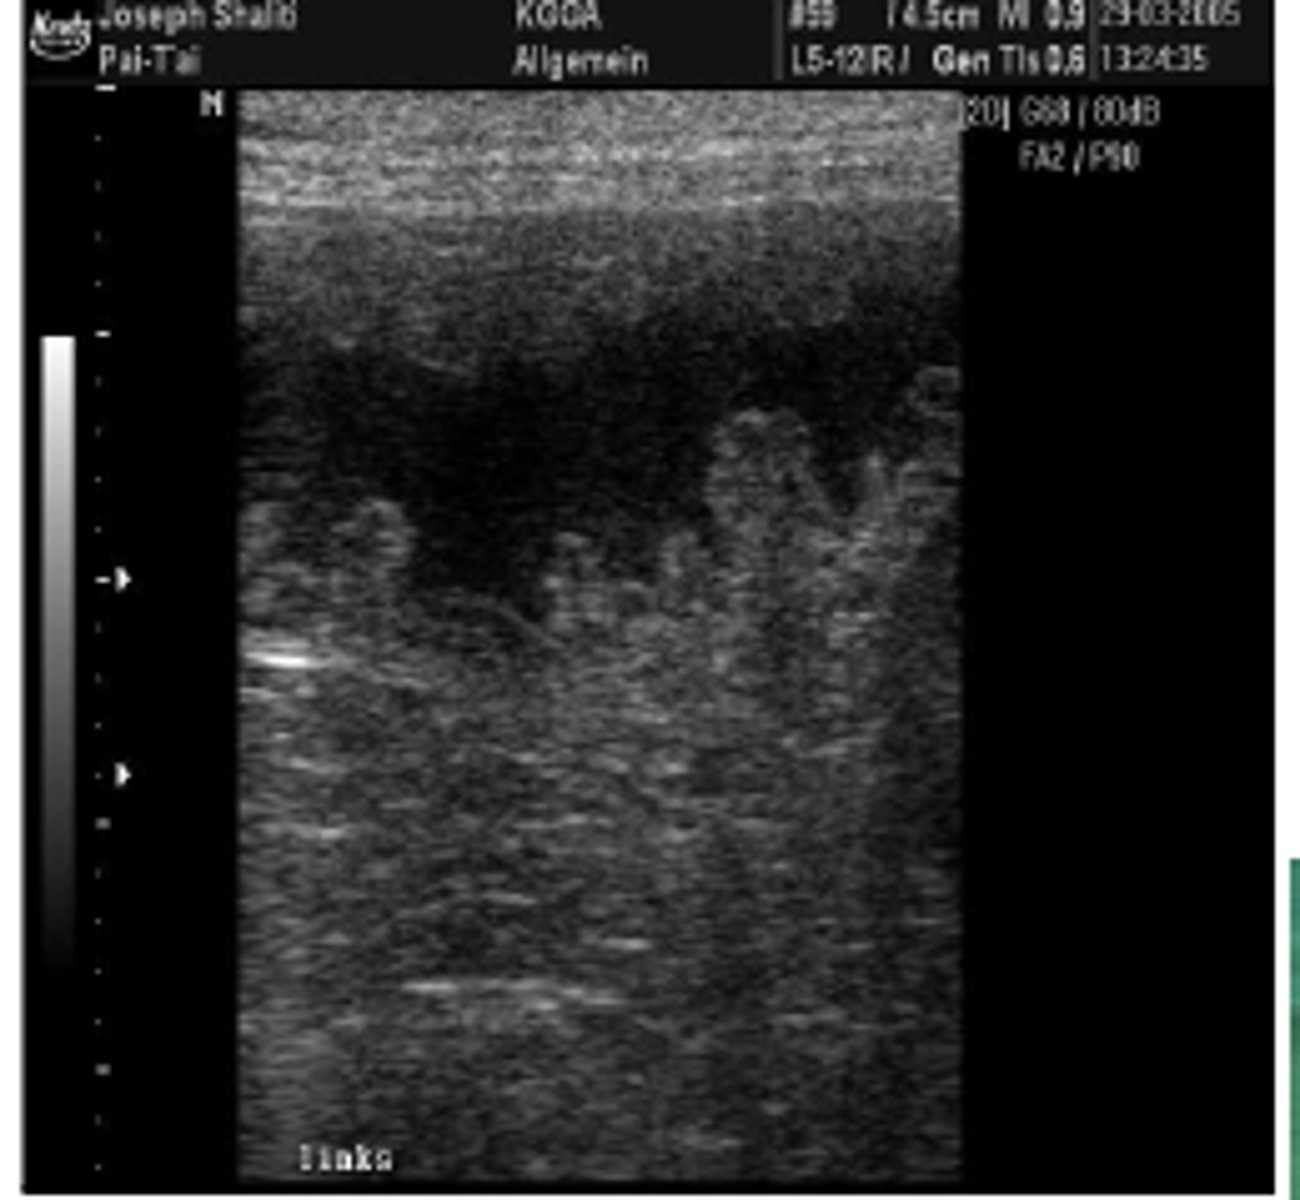

Hvordan stiller man diagnosen pyometra?

ved ultralydskanning

Hvordan stiller man diagnosen ovariecyster og hvilke komplikationer kan disse medføre?

Ved vaginal cytologi eller ultralydsskanning.